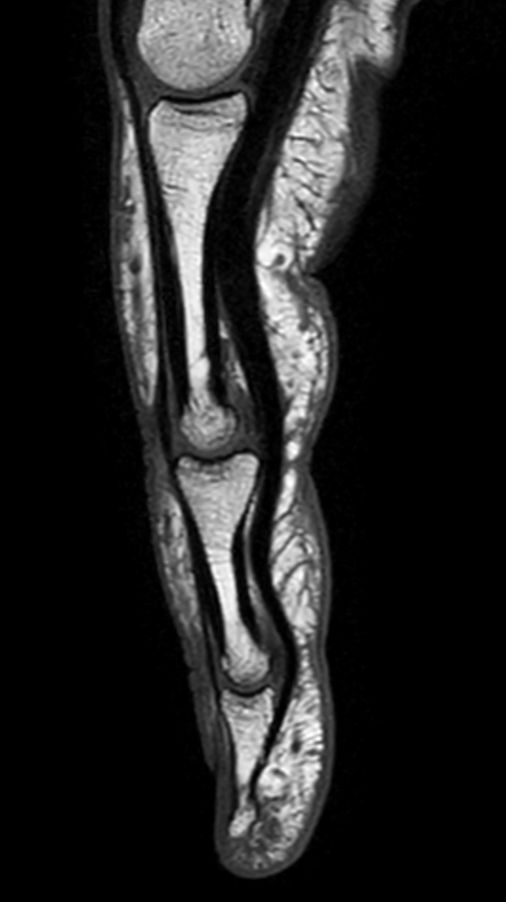

Sagittal T1w TSE